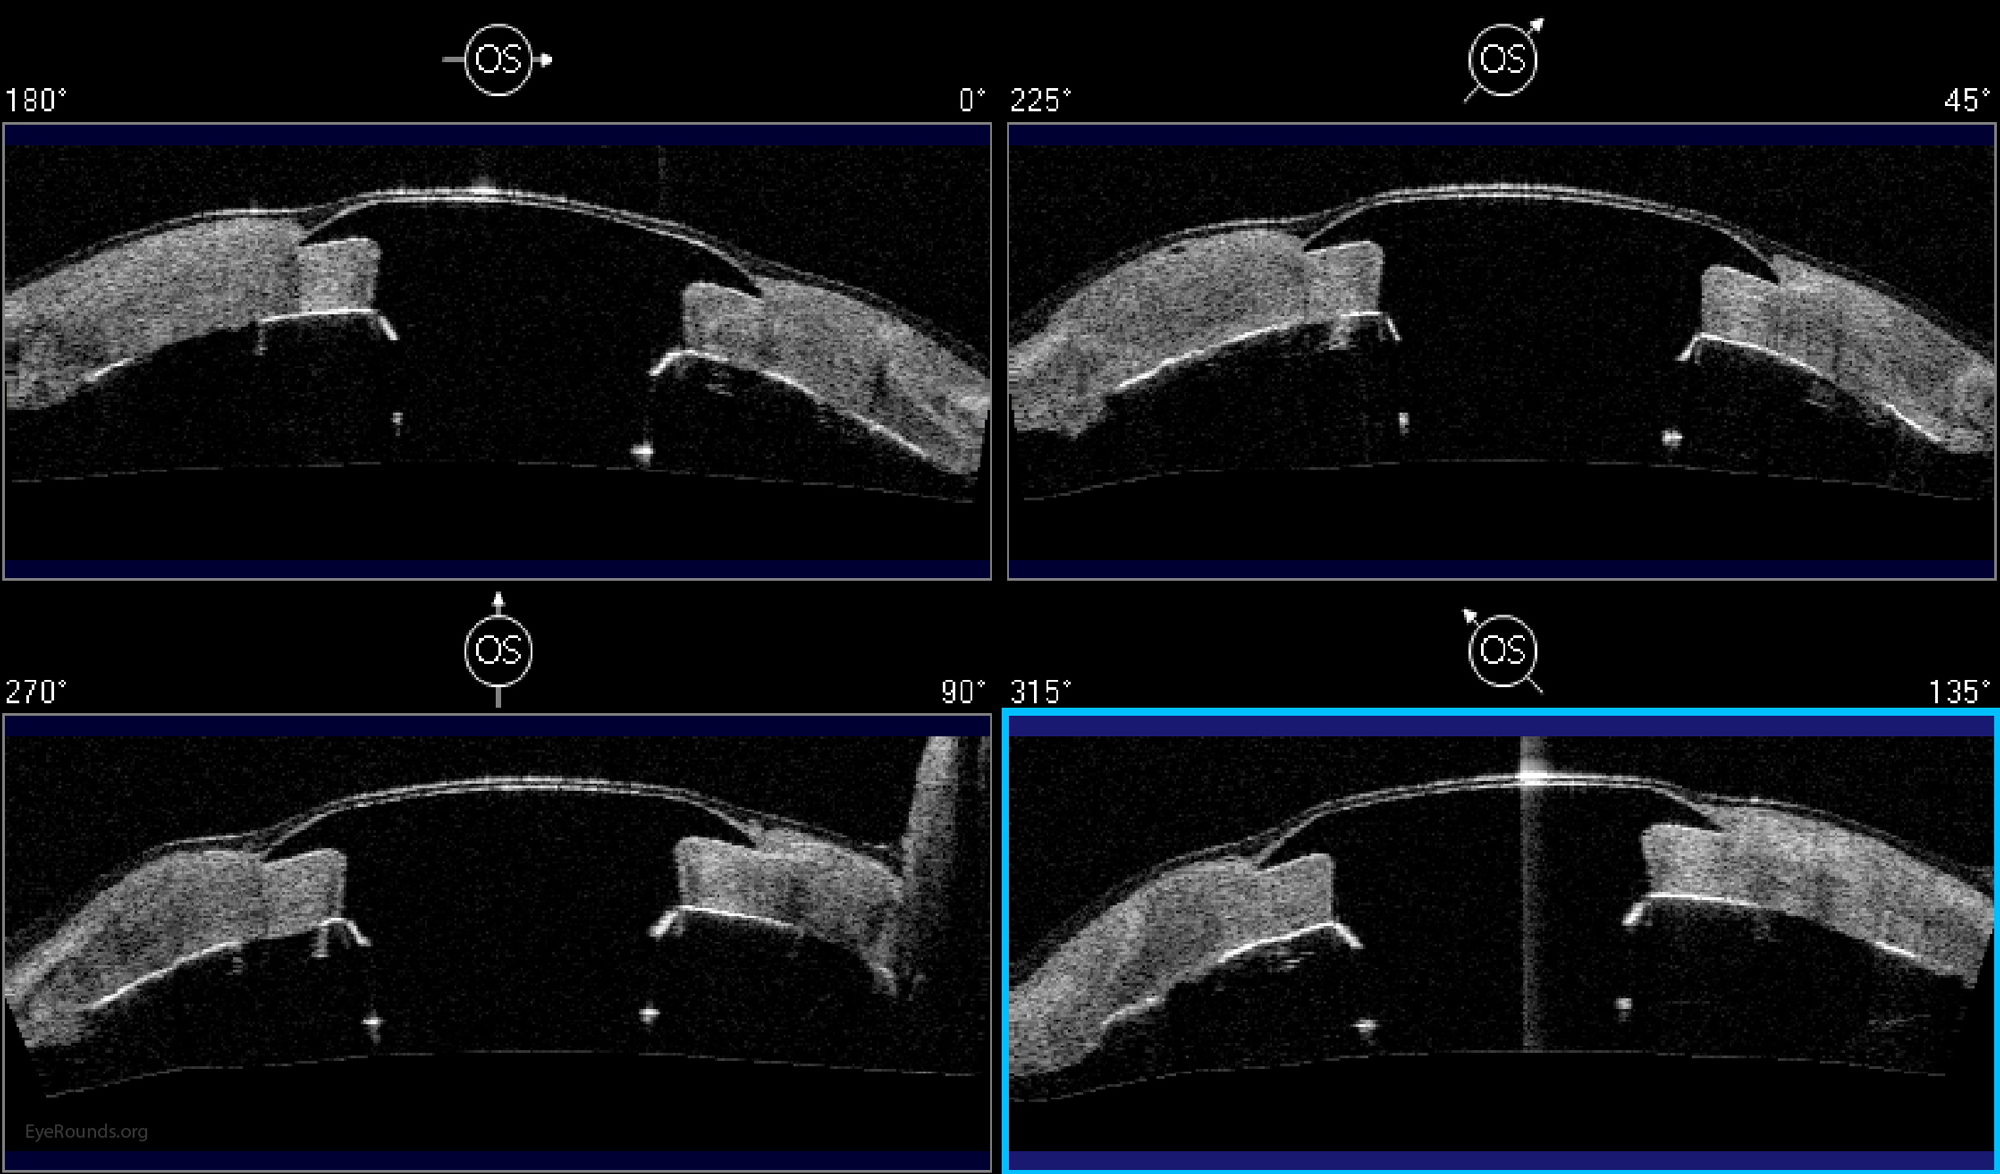

Keratoprosthesis implantation is a procedure that involves full-thickness removal of the cornea and replacement by an artificial cornea. The Boston Type I Keratoprosthesis is currently the most commonly used keratoprosthesis device in the US. It consists of a clear plastic polymethylmethacrylate (PMMA) optic and back plate sandwiched around a corneal graft and secured with a titanium locking ring (Figure 15). After the device is assembled, a partial-thickness trephination is performed on the host cornea. Full-thickness resection of the patient's cornea is then completed using curved corneal scissors. The keratoprosthesis is then secured to host tissue using interrupted or running sutures. Generally, patients who have a history of multiple failed PKs are candidates for a keratoprosthesis transplant. Other indications include severe keratitis or ocular surface disease resulting from limbal stem cell failure, such as Stevens-Johnson syndrome (Figure 16), ocular cicatricial pemphigoid, aniridia (Figure 17) and chemical injury (1, 13). The Boston Type II Keratoprosthesis is a similar device with a longer optic designed to extend through an opening made in the upper eyelid (Figure 19). It is indicated for the most severe cicatrizing ocular surface diseases.

There is significant long-term risk of complications for those with a keratoprosthesis. Because the KPro is a foreign body, there is risk of infection or extrusion of the device. Post-operative glaucoma is common and intraocular pressure is difficult to evaluate as the hard optic makes traditional tonometry impossible. For this reason, glaucoma tube shunts are typically placed at the time of the corneal transplant at the University of Iowa. The Diaton is currently the preferred way to measure intraocular pressure in these patients in our institution. Patients can form retroprosthetic membranes requiring treatment with a Nd:YAG laser or surgical membranectomy (21).